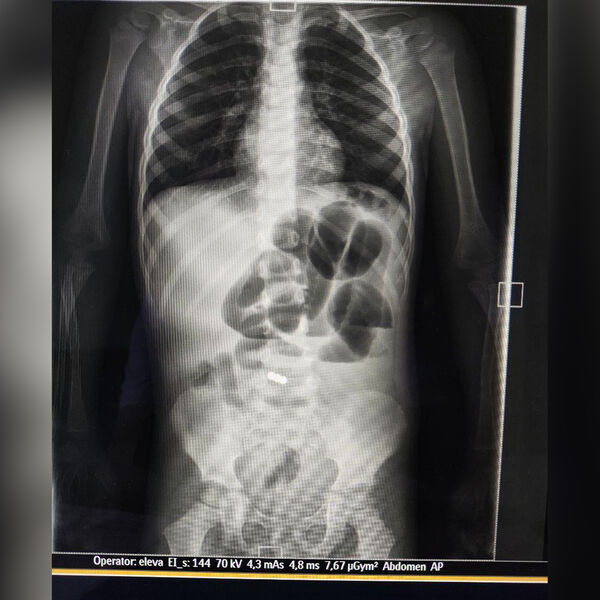

По словам медиков, ребенка привезли в больницу в тяжелом состоянии: его беспокоили боли в животе, многократная рвота. Также температура тела маленького пациента подскочила до 39 градусов. Обследование показало, что в ЖКТ у ребенка застряли три магнитных шарика. Врачи приняли решение об экстренной операции.

«У малыша участок подвздошной кишки с двумя магнитами примагнитился к куполу слепой кишки», — рассказал детский хирург Якоб Горбачев, добавив, что операция длилась два часа.